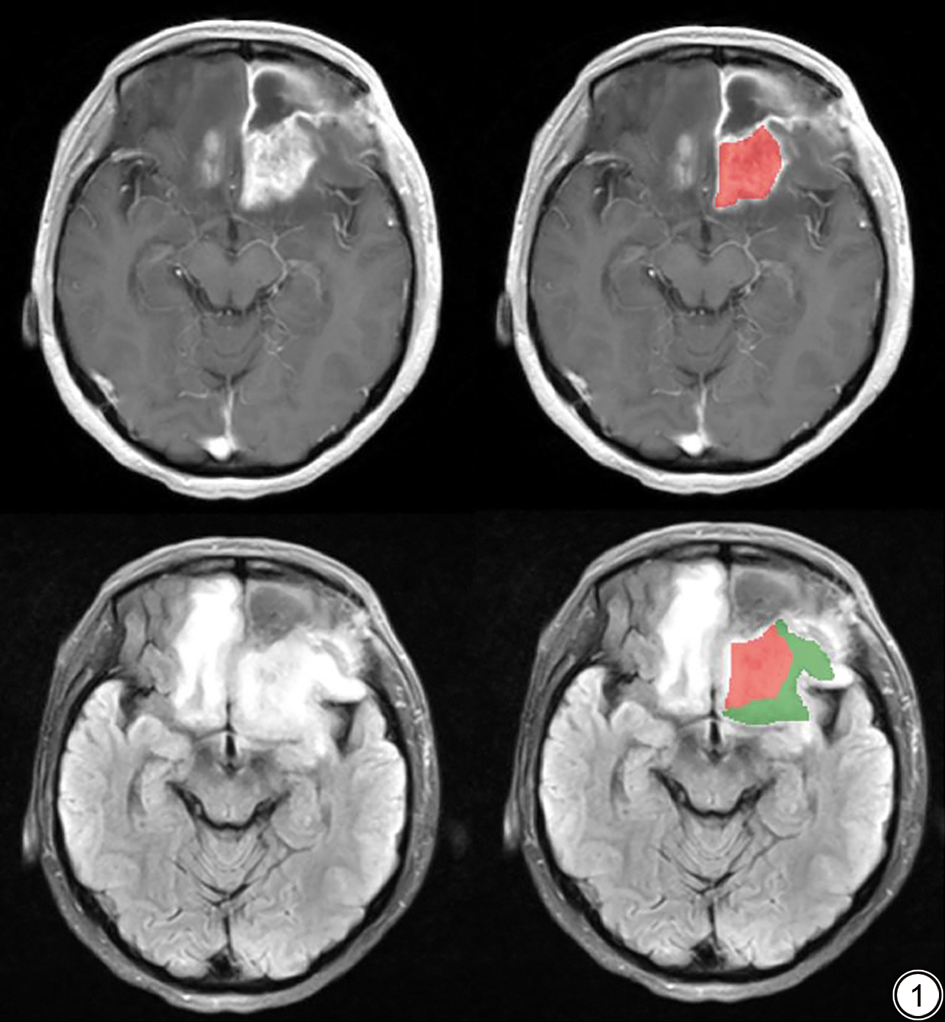

在本研究纳入的106例患者中,TP组65例,PsP组41例,其中二次手术病理证实为TP 9例,证实为PsP 8例,典型影像学表现见图2, 图3。脑胶质瘤术后TP及PsP均表现为术区或邻近脑组织内团块状、斑片状T1WI低信号、T2WI高信号,增强扫描呈明显不均匀强化,均可见占位效应,但肿瘤复发灶周围水肿范围较PsP明显,且病灶大多弥散受限,表现为不同程度的高灌注。患者临床影像资料见表1。2位医师对病灶定位、病灶中心部位的评估一致性良好(Kappa值分别为0.93、0.89,P<0.001),对病灶强化体积测量的一致性优秀(ICC=0.90,P<0.001),表明影像评估结果可靠。

图2  高级别胶质瘤术后复发的典型MRI 表现。图2A~2F 分别为病变在轴位T1WI、FLAIR、ADC、CE-T1WI、CBV、CBV-RGB 序列上的显示。左侧颞叶可见一环形强化灶,灌注呈环形高灌注。FLAIR:液体衰减反转恢复;ADC:表观扩散系数;CE-T1WI:T1 加权对比增强成像;CBV:脑血容量;CBV-RGB:脑血容量彩色图。

Fig. 2  Typical MRI manifestations of postoperative recurrence in high-grade glioma. 2A-2F demonstrate the lesion on T1WI, FLAIR, ADC, CE-T1WI, CBV, and CBV-RGB sequences, respectively. An annular enhancing lesion with peripheral hyperperfusion is observed in the left temporal lobe. FLAIR: fluid-attenuated inversion recovery; ADC: apparent diffusion coefficient; CE-T1WI: T1-weighted contrast-enhanced imaging; CBV: cerebral blood volume; CBV-RGB: cerebral blood volume-red green blue.